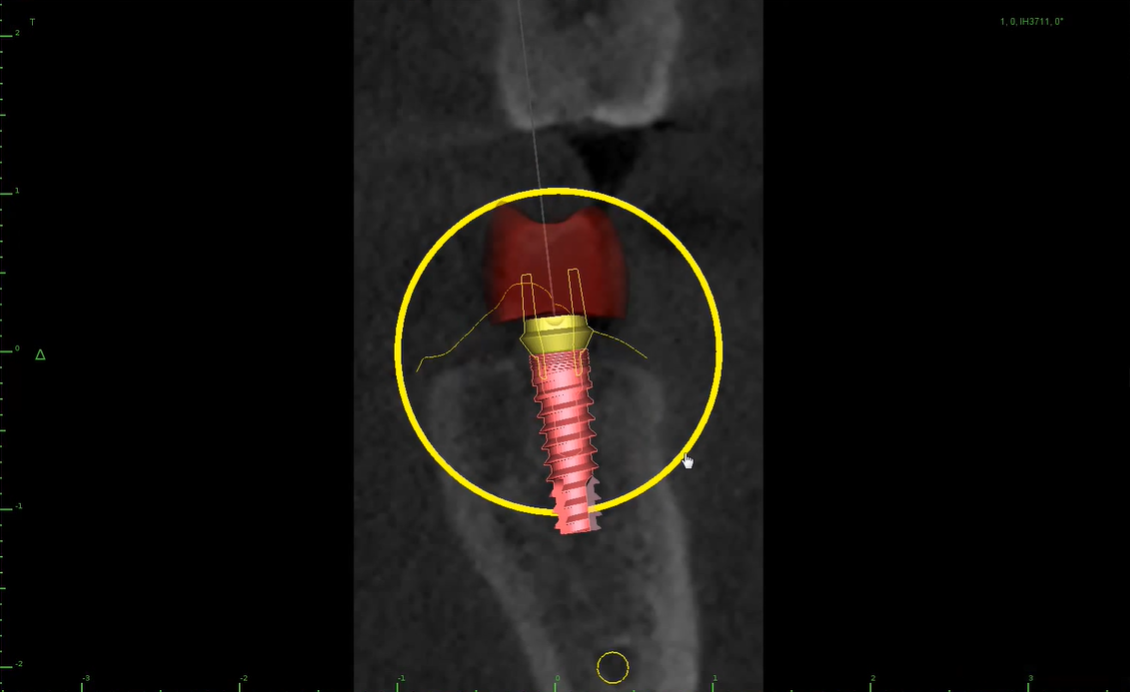

Chirurgia e Implantologia

L'implantologia è una branca della chirurgia odontoiatrica che permette di ripristinare il sorriso dei pazienti che hanno perso uno o più denti. Essa si avvale dell'impianto di denti fissi in modo semplice, sicuro e duraturo nel tempo.

Utilizziamo le più moderne tecnologie,con la chirurgia computer assistita per offrire ai nostri pazienti più precisione e meno traumi. Ci prenderemo cura di te in modo da ricostruire il tuo sorriso.

La Cone Beam 3D è una moderna metodologia diagnostica che consente di riprodurre sezioni o un'immagine del cranio tridimensionale che viene utilizzata, in genere, per l'implantologia.